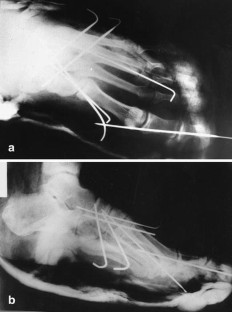

We report an unusual case of concomitant plantar tarsometatarsal (Lisfranc) and 1st and 2nd metatarsophalangeal (MTP) joint dislocations and fracture of the neck of the third metatarsal bone which has never been reported before. The plantar dislocation of the Lisfranc joint was treated by open reduction and fixation with K-wires; the dislocations of the MTP joints and neck fracture of the third metatarsal bone were treated by closed reduction and percutaneous fixation with K-wires and immobilized with a plaster cast. At the 5 year follow-up examination, our patient had no complaints, but the radiograph showed degenerative changes of the Lisfranc and the 1st MTP joint.

Fig. 2a,b.